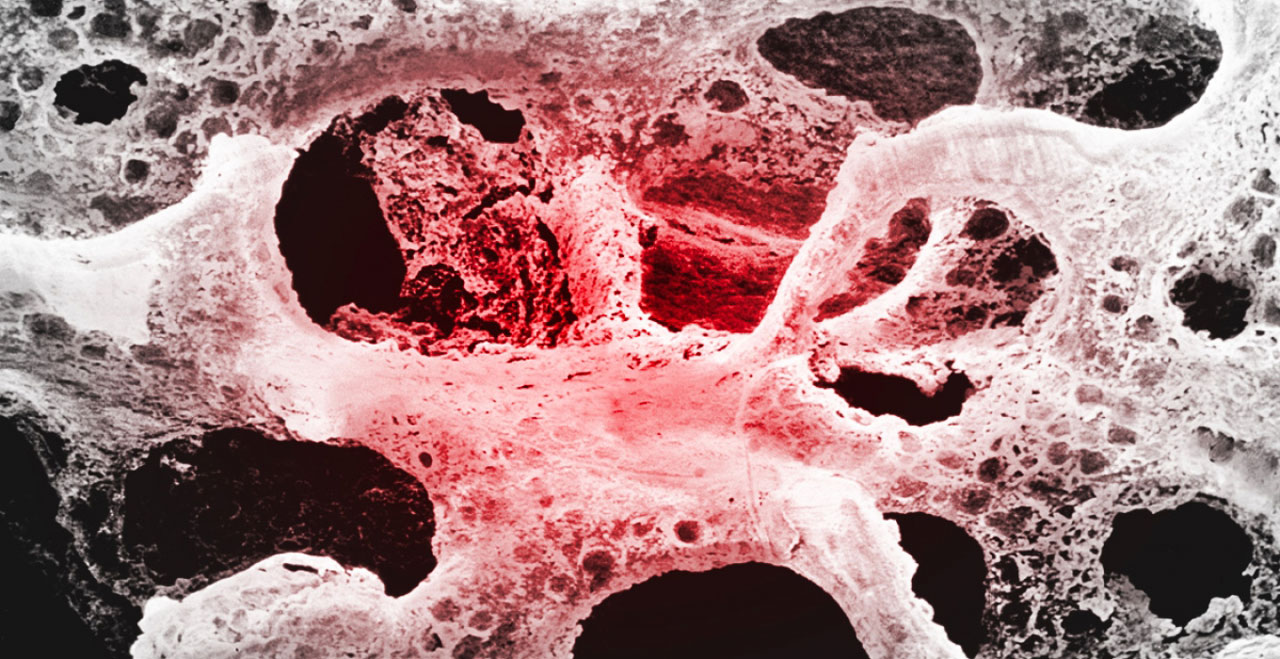

Osteoporosi: cosa succede alle ossa

Uno scheletro colpito da osteoporosi presenta una densità ossea ridotta, che va a compromettere l’intera micro–architettura scheletrica.

Venendo meno questa condizione, le ossa vengono esposte a fratture con maggiore facilità, anche per traumi di lievissima entità.

L’architettura ossea, in pratica, non si forma a causa di un disequilibrio nel processo di rimodellamento osseo.

Il processo di mineralizzazione, cioè la fissazione dei minerali che creano il tessuto osseo, e di rigenerazione non avviene più con la naturale efficienza.